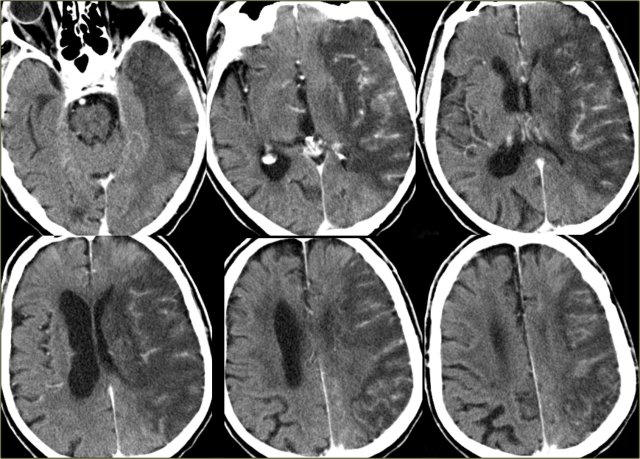

On the left images of a hemorrhagic infarction in the area of the deep perforating lenticulostriate branches of the MCA.

On the left enhanced CT-images of a patient with an infarction in the territory of the middle cerebral artery (MCA).

There is extensive gyral enhancement (luxury perfusion).

Sometimes this luxury perfusion may lead to confusion with tumoral enhancement.